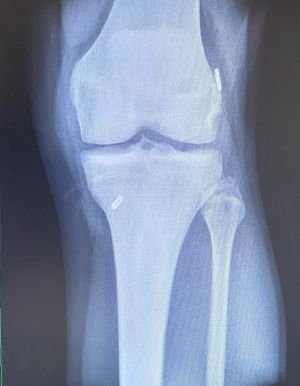

GONARTHROSE UND KNIEPROTHESE

Definition

Die Gonarthrose ist eine Abnützung des Knorpels im Kniegelenk. Dies kann posttraumatisch durch unfallbedingte Schädigung des Knorpels, als auch primär bedingt sein. Als prädisponierende Faktoren zählen dazu Übergewicht oder eine Achsfehlstellung (X- oder O-Bein).

Klinik und Diagnose

Typisch sind belastungsabhängige Schmerzen, anfangs sog. Anlaufschmerzen, später auch Beschwerden in Ruhe. Schließlich kommt es schmerzbedingt zu einer massiven Einschränkung der Gehstrecke. Zudem kann es auch immer wieder zu Ergussbildungen kommen.

Klinisch erfolgt die Beurteilung durch die Anamnese und die Untersuchung. Schmerzen beim Gehen als auch lokale Druckschmerzen über dem Gelenksspalt können festgestellt werden. Weiters können Achsfehlstellungen beurteilt werden sowie Schwellung, Überwärmung, knirschende Geräusche beim Durchbewegen des Gelenkes oder Bandlockerungen aufgrund der Arthrose und Fehlstellung.

Standardmäßig werden Röntgenaufnahmen in zwei Ebenen sowie eine Ganzbeinstandaufnahme durchgeführt. Im Anschluss kann bei noch unklarem Knorpelzustand eine MRT-Untersuchung zur besseren Beurteilung des Schädigungsgrades des Knorpels erfolgen.